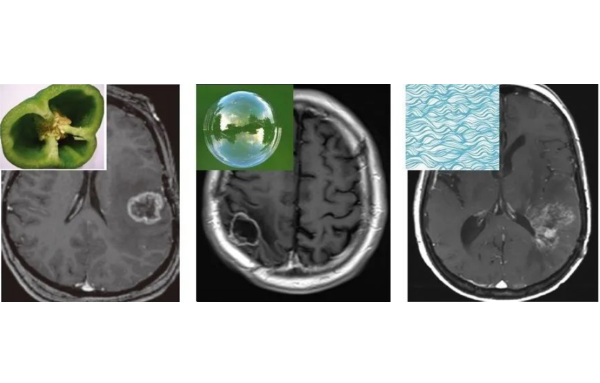

根据影像学表现和特点,晚迟发反应型可分为无病灶期、水肿期、坏死期、囊变期,各期表现可能同时或先后出现在同一患者脑部的不同部位。

3.坏死期:脑组织病灶局部出现坏死,可伴有出血或渗血,头颅MRI显示信号不均,增强扫描可见强化。

4.囊变期:患者头颅MRI显示放射性脑损伤病灶边界清晰并囊性变,信号接近游离水信号,有或无占位效应。囊变期病灶可较长时间稳定,但也可能急性增大,引起脑疝,患者出现意识水平下降,昏迷甚至死亡。